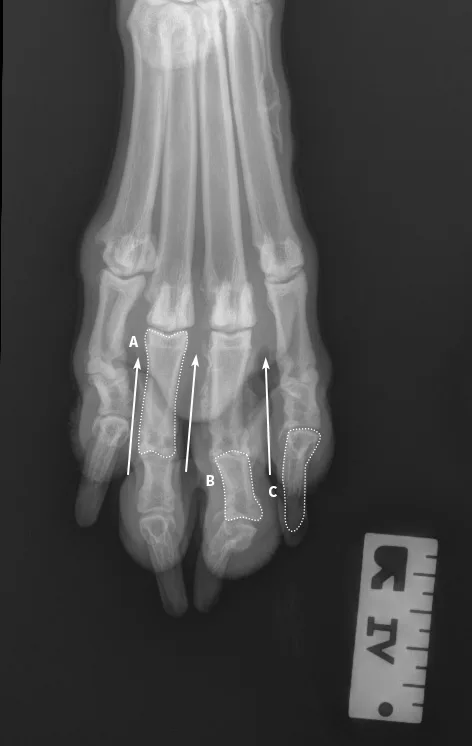

Author Insight

All digits should be separated and clearly visible. The bony edges of the metacarpal bones should be parallel to each other (arrows), and all phalanges (P1 [A], P2 [B], P3 and nail [C]) should be included.